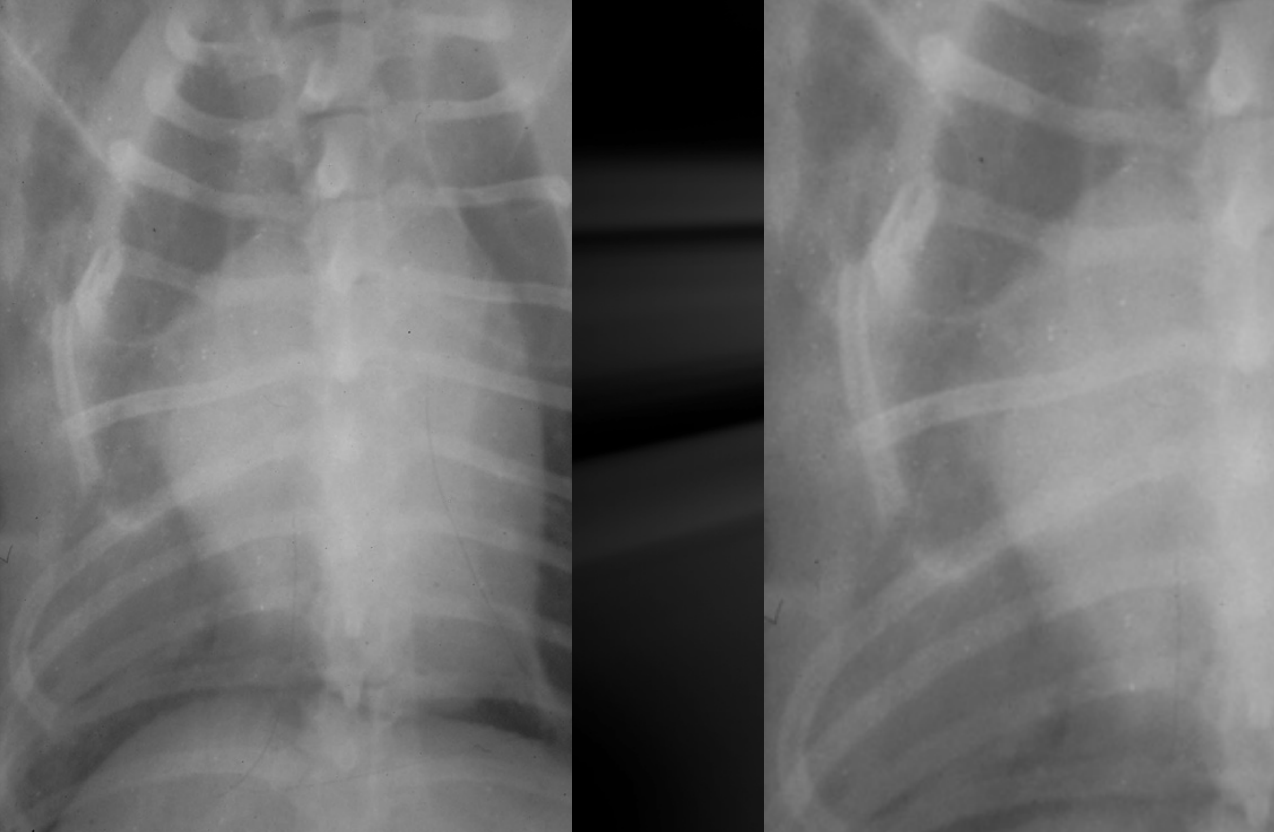

What is shown in these images?

metastatic rib tumors; small, subtle, lytic lesions